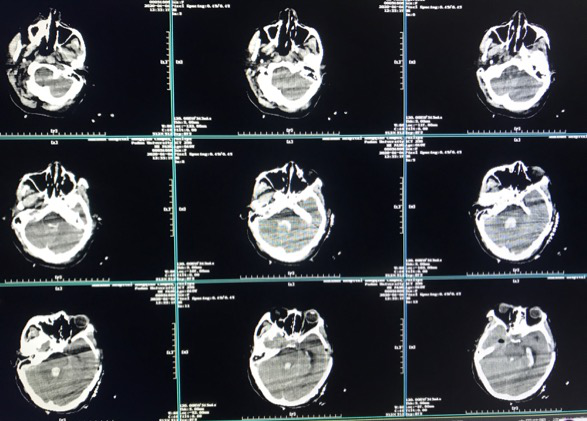

病史

主诉:1月前突发剧烈头痛发作。

查体:GCS 15,四肢肌力正常。

认知功能:MMSE:24;MOCA:25。

既往史: (-)。

烟雾病

脉络膜前动脉假性动脉瘤

术后CT